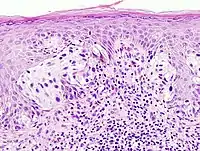

Surgical pathology is the most significant and time-consuming area of practice for most anatomical pathologists. Surgical pathology involves gross and microscopic examination of surgical specimens, as well as biopsies submitted by surgeons and non-surgeons such as general internists, medical subspecialists, dermatologists, and interventional radiologists.

The practice of surgical pathology allows for definitive diagnosis of disease (or lack thereof) in any case where tissue is surgically removed from a patient. This is usually performed by a combination of gross (i.e., macroscopic) and histologic (i.e., microscopic) examination of the tissue, and may involve evaluations of molecular properties of the tissue by immunohistochemistry or other laboratory tests.